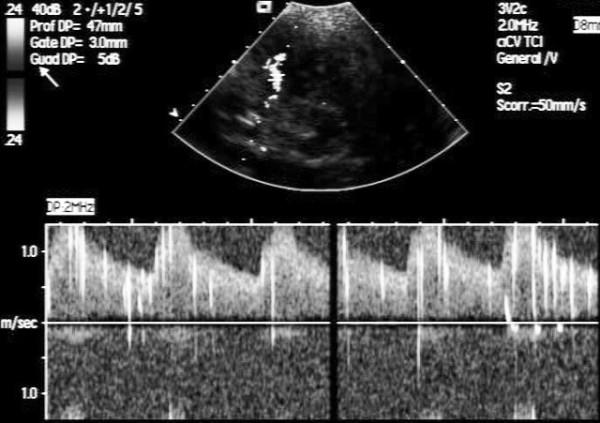

Aortic stenosis and mitral regurgitation, patent foramen ovale, interatrial septal defect, atrial fibrillation and perivalvular leak, are now amenable to percutaneous treatment. These percutaneous procedures require the use of Transthoracic (TTE), Transesophageal (TEE) and/or Intracardiac echocardiography (ICE). This paper provides an overview of the different percutaneous interventions, trying to provide a systematic and comprehensive approach for selection, guidance and follow-up of patients undergoing these procedures, illustrating the key role of 2D echocardiography.

主动脉瓣狭窄、二尖瓣反流、卵圆孔未闭、房间隔缺损、心房颤动及瓣周漏,目前均适合经皮治疗。这些经皮手术需要使用经胸超声心动图(TTE)、经食管超声心动图(TEE)和/或心内超声心动图(ICE)。本文概述了不同的经皮介入治疗,试图为接受这些手术的患者提供一种系统、全面的选择、指导及随访方法,并阐述二维超声心动图的关键作用。